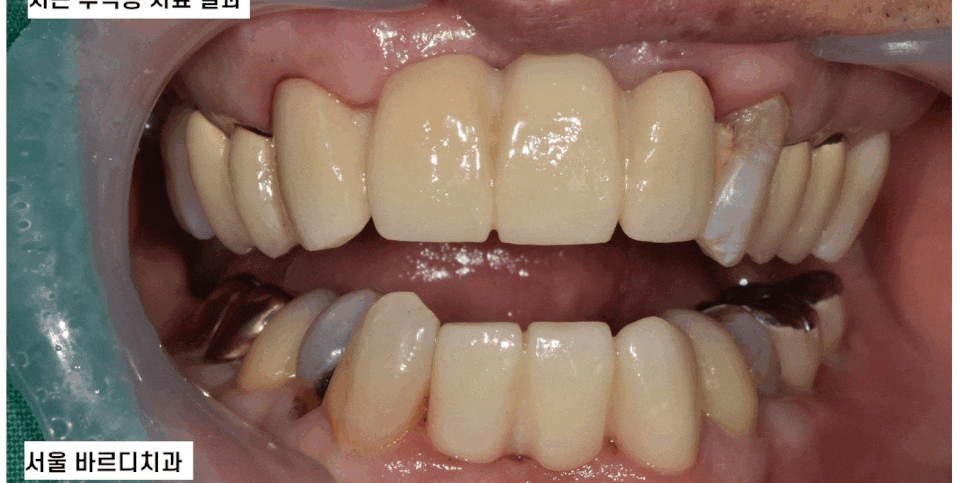

오늘 서울바르디치과를 내원하신 환자분은

입 마름으로 인하여 다발성 치근 우식증이 있었는데요.

뒤늦게 내원하셔서 증상이 심각하였고

(이미 부러진 치아도 있었어요ㅠㅠ)

신경치료 후 보철 치료로 진행할 수밖에 없었답니다.